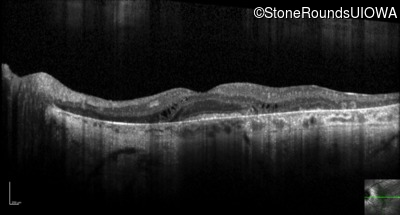

Optical Coherence Tomography - Right - 20/50 -1 sc

Exemplar / OCT Stack

OCT Stack